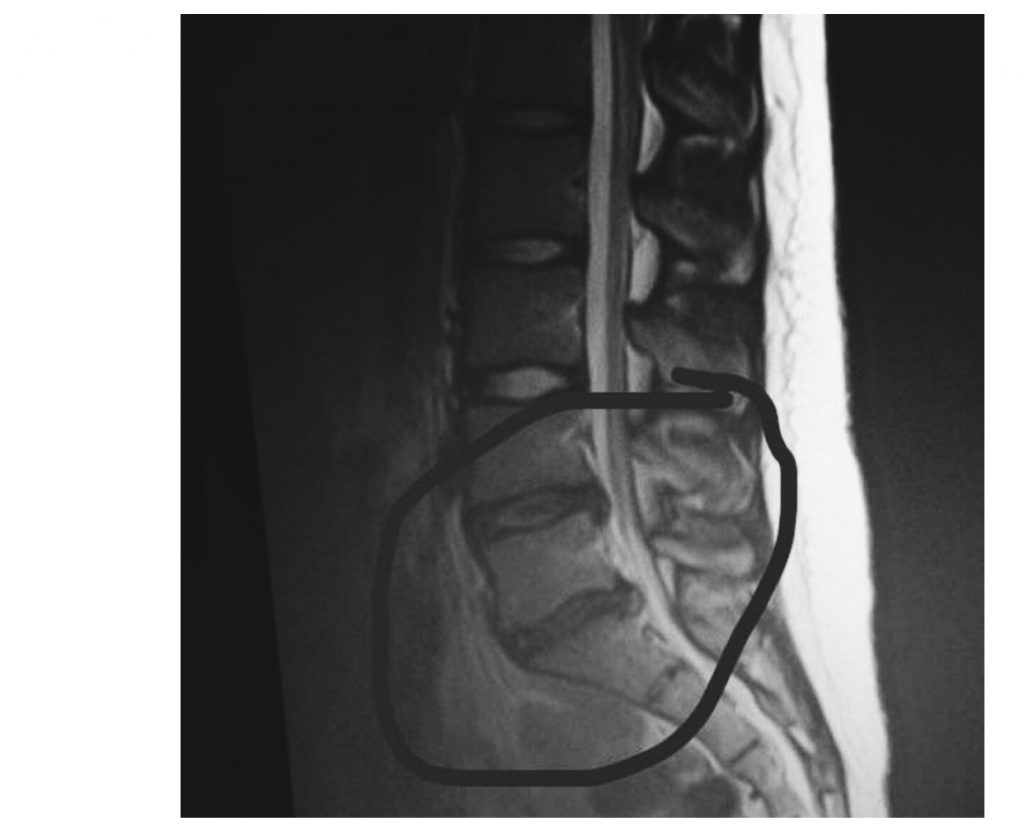

Herniated Disc (Bulging Disc)

Although this long journey is not over I'm still proud of the strength my tiny 2 inch scar represents. The strength to now embrace my body in all different ways, stretch marks, beauty marks, rolls of fat, and scars that came along with walking into walls to spine surgery. The strength to recover and grow from such pain. The encouragement of your own tears falling down to your feet trying to make it up that one step. The strength to be vulnerable in the darkest of times. Including catheters, bed pans, being stripped naked out of your own vomit, and the inability to shower alone, but most of all the strength to own my story and keep going. Through pain and struggle there is strength and courage. When you reach that goal you fought so hard for, there is no better feeling than that defying moment (April 9th, 2017 stepping in a game for the first time after 386 days ). Don't let anything stop you from overcoming obstacles that life throws at you, no matter how scary it might seem. (Even if you have to walk through high school with a rolling back pack and a pillow ?). You never know how strong you are until being strong is the only option you have left. Never give up. See your worth and know that your beautiful with your flaws and all ???? I couldn't have come this far without the support of my beautiful friends and family, but most certainly the one I will never be able to thank enough Dr. Han Jo Kim. #hospitalforspecialsurgery?